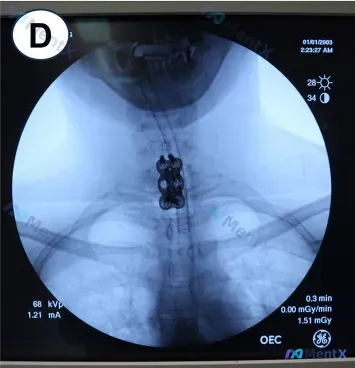

整理到一份颈椎病例的影像与手术资料,第一眼位置看起来还行,但结合临床背景其实很有讨论价值。 基本信息 - 手术方式:C7 次全切除术,钛网填充人工骨,C6、T1 各置入 2 枚螺钉,钛板固定 - 影像:颈胸段正位透视图像 影像所见(摘要) - 金属内固定系统(钢板+螺钉)位于脊柱中线,位置居中 -...